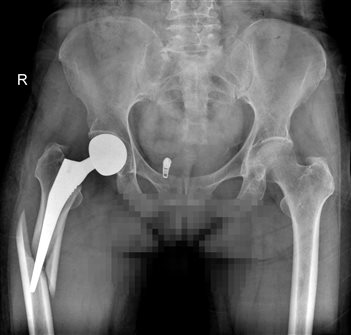

患者吴女士,在做髋关节置换术3周后不慎摔倒,当时髋部、大腿疼痛,下肢不能活动。患者家属了解到我院外二科苏纯柱主任在骨科疾病的治疗方面经验丰富,手术效果非常好。患者家属立即联系苏纯柱主任,苏纯柱主任了解到患者病情后,初步考虑患者存在两种情况:①髋关节脱位②髋关节假体周围骨折。患者来院后拍片检查证实患者假体周围骨折,患者骨折移位明显,严重影响生活质量。

苏纯柱主任介绍随着人口老龄化及人工关节的普及,假体周围骨折的数量逐年上升,由于患者多为老年人,伴有骨量减少、骨质疏松、骨质丢失严重;假体周围骨折的治疗比较复杂。本例患者髋关节置换术后3周,结合拍片考虑患者假体稳定,因此不需要处理髋关节假体,仅行假体骨折固定即可达到满意效果。